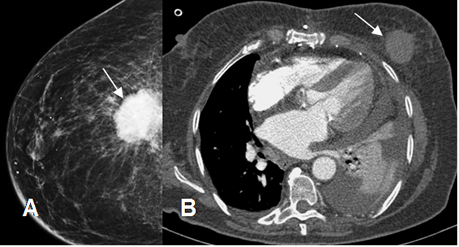

Fig 221. Neoplasia de mama.

A: Mamografía y B: TAC axial. Masa densa y espiculada en la región profunda de la mama, por neoplasia. En la TAC hay además atelectasia y derrame pleural, por enfermedad metastásica.